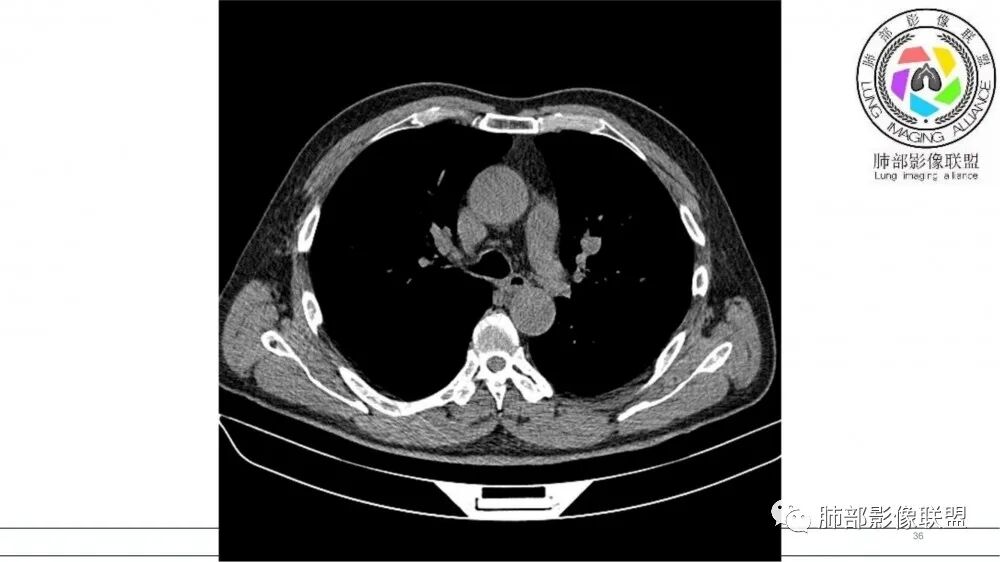

左肺上叶前段支气管内铸形生长软组织影,增强后均匀强化,远侧见斑片状磨玻璃影。考虑恶性病变,粘表?粘液腺?

老年男性,左肺上叶前段支气管内铸形阴影,增强后病灶不均匀强化,内部有坏死?远端可见斑片状阴影(阻塞性肺炎)。考虑恶性病变,老年人,鳞?类癌?粘表不能排除。

有强化吧,淋巴结大

指套征,扩张支气管内软组织强化,远侧肺野阻塞性炎,纵隔、左肺门肿大淋巴结;老年男性,吸烟,考虑鳞癌,鉴别小

老年男性,术前检查肺气肿背景,左肺上叶结节,沿支气管蠕虫样生长,左肺门及纵隔淋巴结肿大,增强扫描不均匀强化,血管包绕,结合吸烟史,考虑小细胞肺癌。

研究报道,中心型 SCLC 经 CT 扫描后通常支气管表现为鼠尾样狭窄,肺门或纵隔肿块明显,由于肿块沿管壁生长表现为顺延支气管形态的不规则形状。病灶相对特征性影像学表现比如鸭蹼状、腊肠状、葫芦状及葡萄状改变,可以出现血管包埋,很少有空洞、空泡,较少引发肺不张,阻塞性炎症成都较轻。与一般肺癌比较,恶性程度高,侵袭力强、病灶很小就容易远处转移!Herzberg 等[19]研究指出,20%以上 SCLC 倍增时间短,预后不良。

胸部平扫及增强CT常能发现并确定肿瘤位置、肿瘤特点和累及的范围及远处转移情况。运用胸部增强CT可明显缩小鉴别诊断的范围,而使部分患者可达到早期诊断;免疫组化病理特征可增强 SCLC 诊断阳性率,为鉴别诊断与组织学分型提供参考。